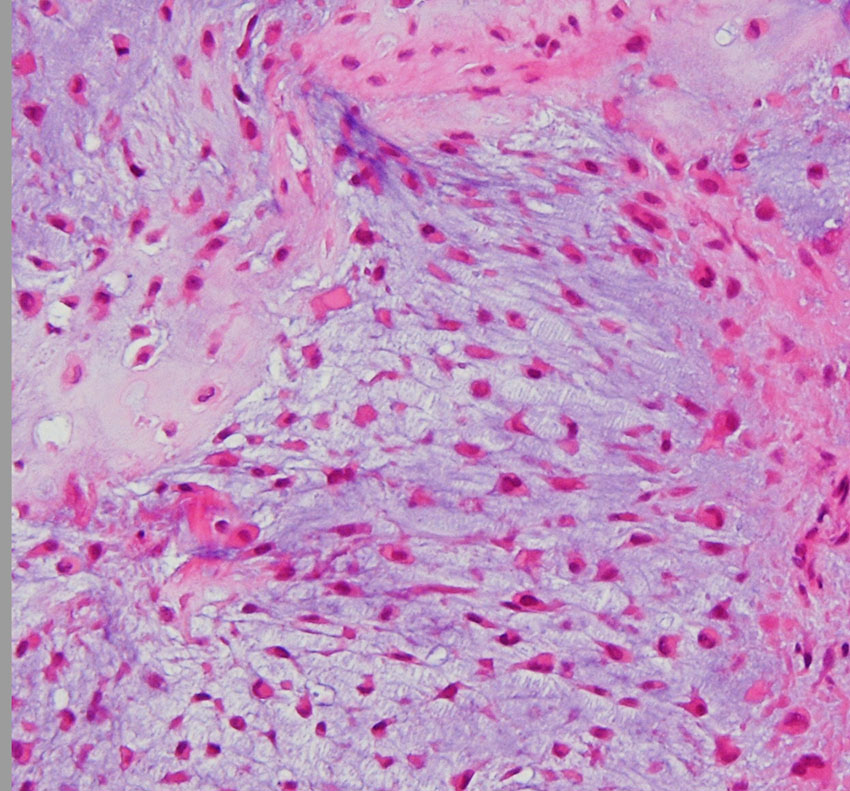

低悪性度軟骨肉腫の病理像 grade 2 chondrosarcoma

背景は好塩基性の軟骨基質(粘液状 myxoid,軟骨様 chondroid)です。好酸性胞体をもつ異型紡錘形ないし上皮様細胞が多結節状に増殖しています。細胞密度はやや高い部分もあり,核は濃縮され大小不同や2核の細胞も見られます。MIB-1 index 3%